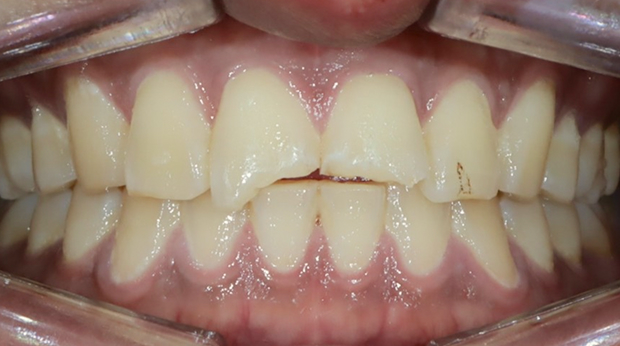

라미네이트

임플란트와 사랑니 발치는 외과적 시술로 잇몸을 절개하는 외과적 시술은